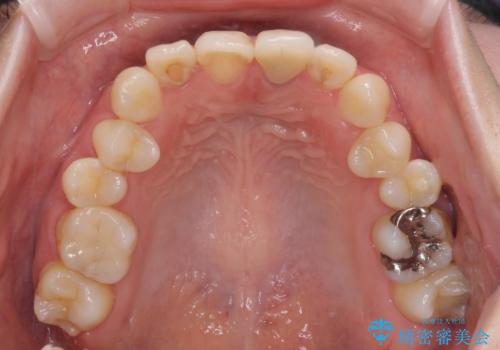

- 前歯のクラウン付近の歯肉が黒く見えることを気にして来院された患者様です。

根管治療を行った後に、オールセラミッククラウンにて補綴することとしました。